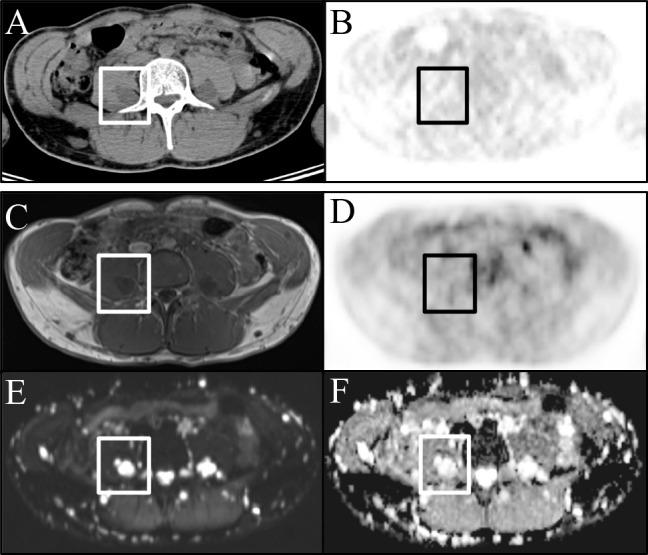

Patients diagnosed with neurofibromatosis type 1 and peripheral nerve sheath tumors (PNST) were enrolled in this prospective, IRB-approved study. After a single [F18]-FDG injection, patients consecutively underwent [F18]-FDG-PET/CT and [F18]-FDG-PET/MRI on the same day. Maximum and mean standardized uptake values (SUVmax, SUVmean) on [F18]-FDG-PET/CT and [F18]-FDG-PET/MRI were compared, and correlated with minimum and mean apparent diffusion coefficients (ADCmean, ADCmin).

A total of 12 (6 male/6 female, mean age was 16.2 ± 5.2 years) patients were prospectively included and analyzed on a per-lesion (n = 39) basis. The SUVmean of examined PNST showed a moderate negative correlation with the ADCmean (r = -.441) and ADCmin (r = -.477), which proved to be statistically significant (p = .005 and p = .002). The SUVmax of the respective lesions, however, showed a weaker negative correlation for ADCmean (r: -.311) and ADCmin (r: -.300) and did not reach statistical significance (p = .054 and p = .057). Lesion-based correlation between [F18]-FDG-PET/MRI and [F18]-FDG-PET/CT showed a moderate correlation for SUVmax (r = .353; p = .027) and a strong one for SUVmean (r = .879; p = .001)). Patient-based liver uptake (SUVmax and mean) of [F18]-FDG-PET/MRI and [F18]-FDG-PET/CT were strongly positively correlated (r = .827; p < .001 and r = .721; p < .001) but differed significantly (p < .001).

We found a statistically significant, negative correlation between glucose metabolism and cell density in PNST. Thus, ADCmean and ADCmin could possibly add complimentary information to the SUVmax and SUVmean and may serve as a potential determinant of malignant transformation of PNST.